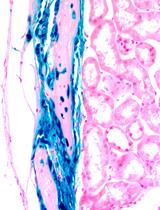

Murine Hair Follicle Derived Stem Cell Transplantation onto the Cornea Using a Fibrin Carrier

使用纤维蛋白载体将小鼠毛囊源性干细胞移植到角膜